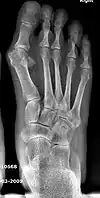

Before_syndesmosis_surgery

Fig. 4a: Before surgery

2_years_after_syndesmosis_surgery

Fig. 4b: 2 years after surgery

Syndesmosis procedure addresses specifically the two fundamental problems of metatarsus primus varus deformity that gives rise to the bunion deformity. They are leaning and instability of the first metatarsal bone . Syndesmosis procedure uprights the leaning first metatarsal bone with strong binding sutures between it and the second metatarsal bone (Fig. 2) and then also stabilizes it uniquely by creating a fibrous connecting bridge between these two bones (Fig. 3, 4). First metatarsal bone can be readily realigned because by definition of the metatarsus primus varus deformity its first metatarsal is abnormally loose and mobile.